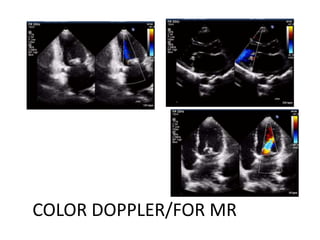

COLOR DOPPLER/FOR MR

OTHER 2D FEATURES

• Dilated LA(20-60ml

normal)

• LA and LA appendage

thrombus

• Paradoxical septal

motion

• Dilated RV and RA